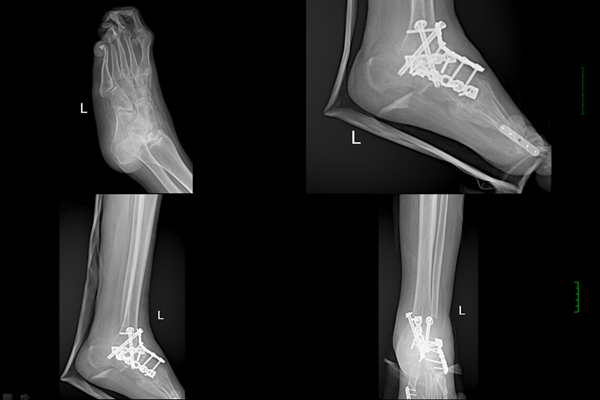

在家人的陪同下,刘永环老人于6月来到我院骨四肢二区进行了首次手术:成人先天性马蹄内翻足四关节融合术及?外翻关节融合术。经过丰哲教授的精心设计和手术,经外侧腓骨截骨手术入路,进行截骨矫形及四关节融合及?外翻第一跖趾关节融合术。手术取得圆满成功, 刘永环老人的脚畸形得到矫正,她为此笑得合不拢嘴。经过骨四肢二区医护人员的精心护理,刘永环老人于六月底带着石膏康复出院。

刘永环老人足部术前X光片

刘永环老人足部术前术后X光片对比